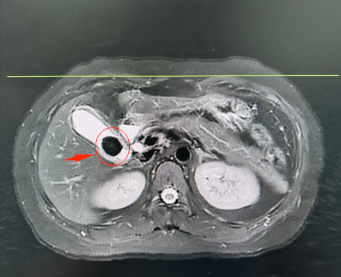

秦女士胰胆管水成像图片,红圈部分为结石

3年前的一次体检中,秦女士被查出胆囊内有一颗0.5厘米的小结石,当时并未放在心上。谁曾想,这颗“小石头”竟在三年间悄然生长,最终发展为直径超过2.5厘米的巨大结石!更令她煎熬的是,结石总在凌晨两三点“作祟”——突如其来的右上腹绞痛让她冷汗涔涔、彻夜难眠。